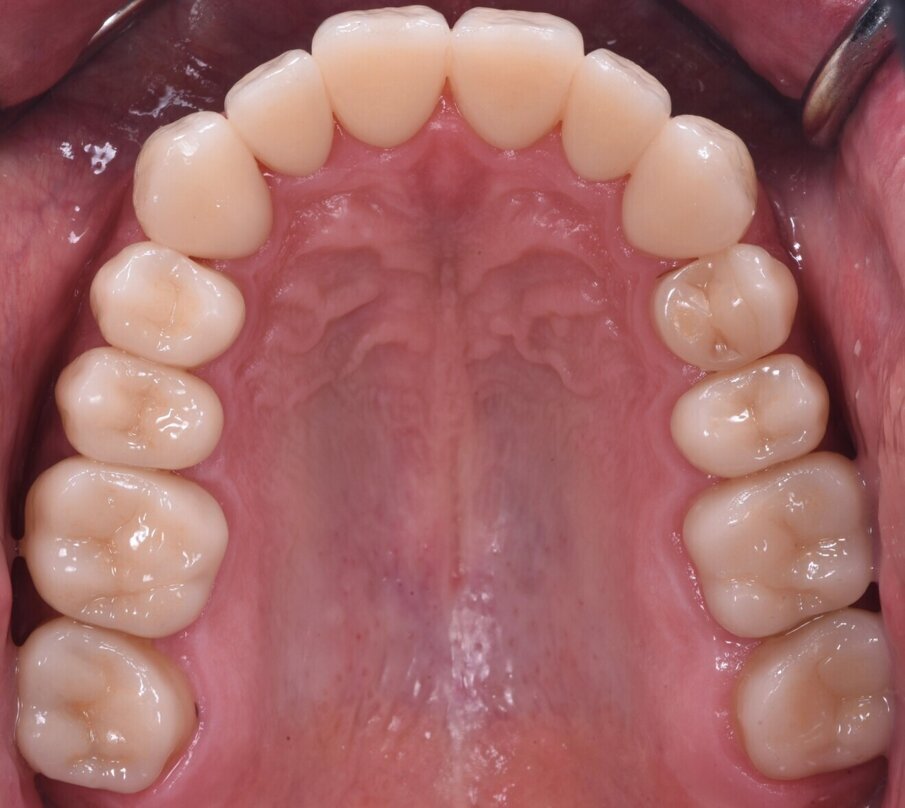

Následně byl zhotoven digitální wax-up ve frontálním úseku horní čelisti, aby bylo možno ověřit estetiku plánované rekonstrukce a vést minimálně invazivní preparaci zubů na základě zhotoveného mock-upu (obr. 8). Finální preparace (obr. 9) se z větší části omezila na interproximální oblasti (obr. 10). Poté byl proveden finální digitální otisk při aplikaci retrakční niti. (obr. 11).

Obr. 8a, b: Anteriorní wax-up.

Obr. 8c–e: Anteriorní mock-up.

Obr. 9a–f: Vodicí drážky pro preparaci.

Obr. 11a a b: Digitální otisky předních čelistních korunek.